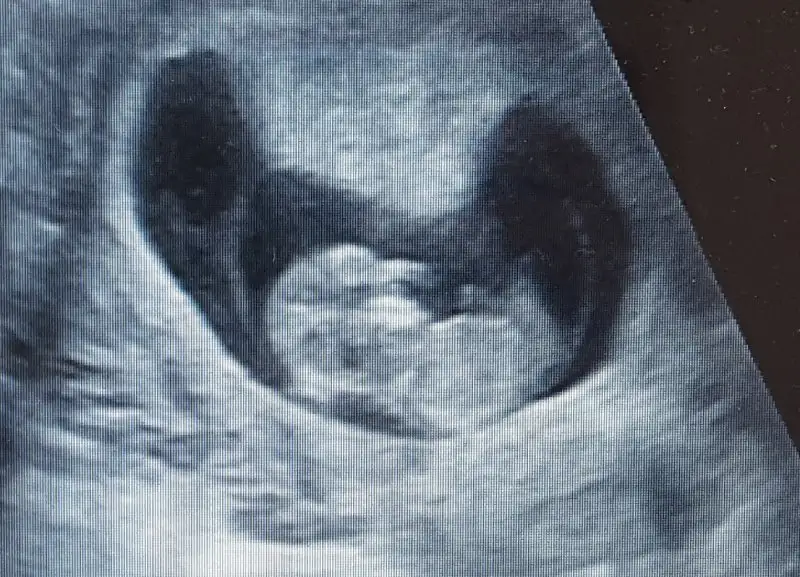

Bebegin Kesedeki Konumuna Göre Cinsiyet Tahmini

Canım keseye göre erkek olabilir

Benimki ne olabilir acaba çok merak ediyorum